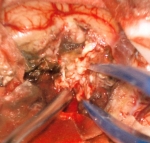

No.359 モニタリング

No.359 手術前

No.359 手術中

No.359 手術後

出血既往があり。2回の手術前血管内手術の後に、

Lateral transpeduncular approachにより再々出血予防を目的に

摘出手術を行う。完全摘出であることを確認した。

手術による合併症や後遺症なしで退院した。経過良好。